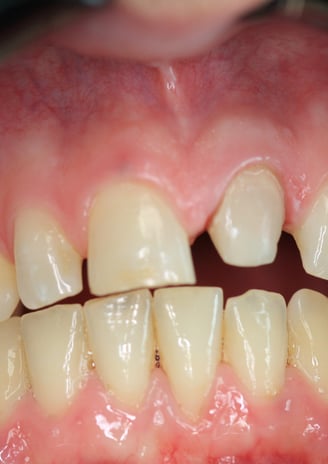

Corona Estetica

Condizioni Finali

La sostituzione della corona su un incisivo centrale richiede un approccio multidisciplinare che coniughi precisione clinica ed eccellenza estetica. In questo caso, il ritrattamento endodontico, la sostituzione del perno moncone e la realizzazione di una nuova corona in disilicato di litio hanno permesso di ottenere un risultato ottimale sia dal punto di vista funzionale che estetico.

Grazie all'impiego di materiali avanzati e tecniche minimamente invasive, è stato possibile garantire al paziente una riabilitazione duratura, ripristinando la stabilità protesica e l’armonia del sorriso. Questo caso conferma l'importanza di una diagnosi accurata e di un piano di trattamento personalizzato per risolvere definitivamente le problematiche legate alle corone incongrue.